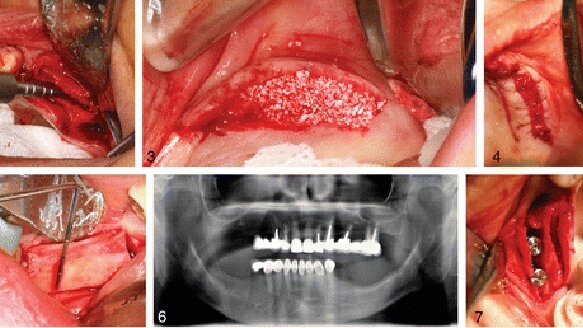

The Journal of Oral Implantology представя подробно описание на алвеоларна сплит процедура, придружена от снимки. Алвеоларният гребен е костното било на горната и долната челюст, което съдържа алвеолите на зъбите. Създаването на алвеоларен гребен с подходящи размери е от съществено значение с появата на ендоосалните дентални имплантати с форма, наподобяваща зъбния корен, най-често използваният тип имплантати.

Алвеоларната сплит процедура, описана в тази статия, е вариант на разширяване и аугментация на билото. В случаите на тесни алвеоларни гребени тя е доказала, че е успешна. Използването на тази минимално инвазивна техника има много предимства в предпротетичния етап на денталните импланти. Сред предимствата на процедурата са нисък риск от нараняване на n. alveolaris inferior, по-малко болка и подуване и липса на нужда от втора хирургична интервенция от донорско място.

Поради различията в плътността на костите алвеоларната сплит техника изисква един хирургичен етап в максилата, и двуетапен подход в мандибулата. Двата етапа при мандибуларната хирургична техника се състоят в кортикотомия – процедура по разсичане на костта, последвана от сплит процедура и аугментация 3 до 5 седмици по-късно. Поетапният подход на алвеоларната сплит процедура е показал висок процент успеваемост при имплантирането и добро запазване на букалната кортикална кост.

Опитът на лекаря е важен компонент при тази техника. Тази операция променя конфигурацията на костта, обикновено не се отварят ламба, а се разчита на тактилното усещане на оператора. Авторите подчертават необходимостта от внимателна работа при наличие на тънко било, познания за прецизни хирургични принципи и специализирано обучение.

Пълният текст на статията „Хоризонтална аугментация чрез алвеоларна сплит процедура – предвидима хирургична модалност при възстановяване с имплантати“, Journal of Oral Implantology , Vol. 39, № 1, 2013 г., е на разположение в http://www.joionline.org/doi/full/10.1563/AAID-JOI-D-12-00112